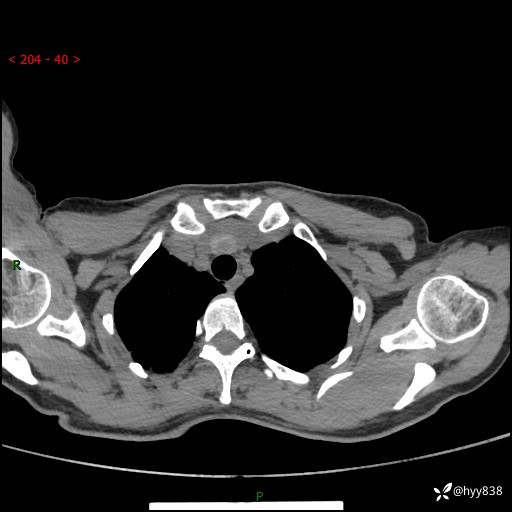

增强动脉期+静脉期